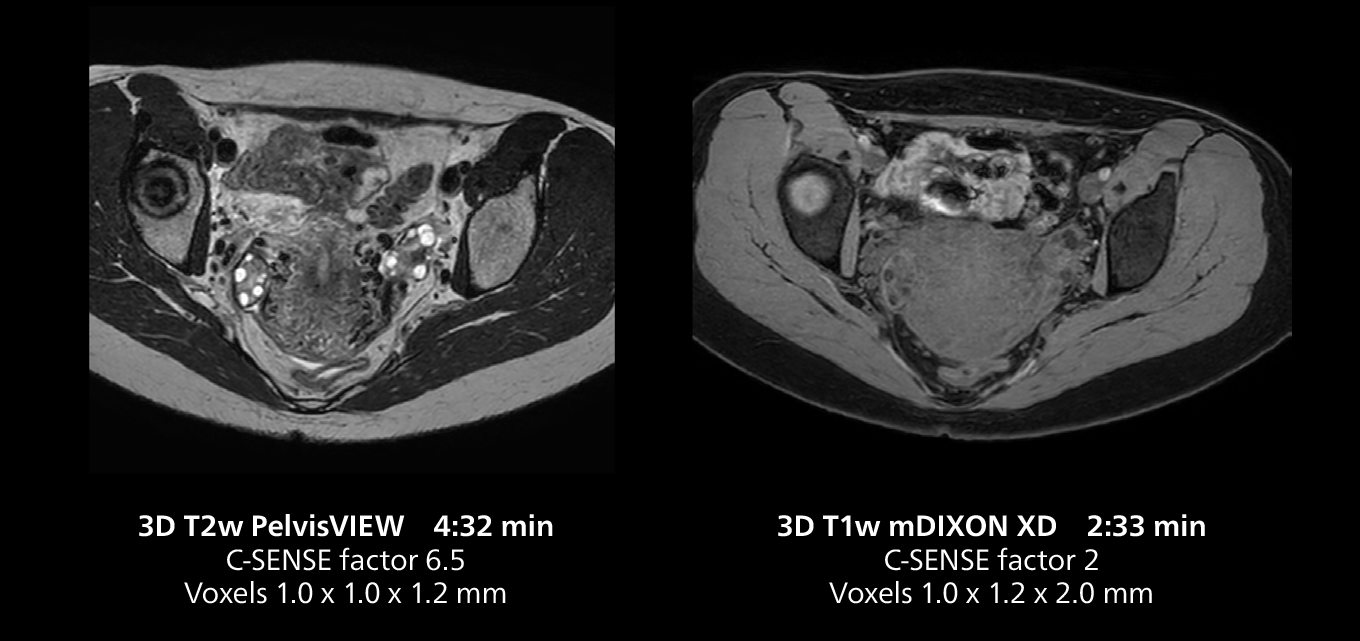

The isotropic high resolution 3D sequence in this MRI case allows for reformatting to obtain other orientations with high quality. Acquired on the MR 5300 system.

Dr. Gellée highlights the robust free-breathing scans as “the feature that makes the biggest difference in my daily work. The 3D free breathing sequences are very reproducible, and the axial acquisition is very good. For example, in endometriosis, which is one of my focus areas, it provides high contrast and good resolution so that I can see small details. We also use free breathing for liver and pancreas imaging. In multi-phase liver studies, 4D Free Breathing delivers 3-second temporal resolution, making a dynamic scan with more than one arterial phase possible.”

“We have more speed in 3D sequences,” Dr. Gellée states. “With Compressed SENSE, we can replace two or three 2D scans withone high-quality 3D scan. High quality additional orientations are then obtained by post-processing of the 3D data set, thus saving scanning time.”